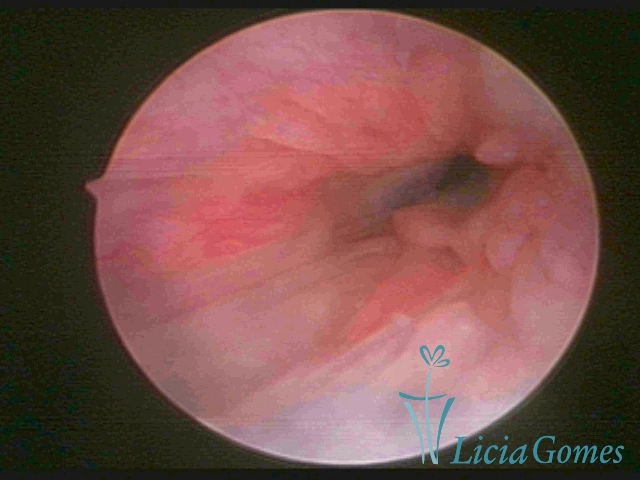

The cervical canal is different during menacme and menopause. In hysteroscopy, the cervical canal is commonly divided into three parts:

First part or proximal section or lower section:

During the proliferative phase, a light, crystalline mucus with a low adherence to the scope is found. The crypts and buds are a little swelled and vascularized, microvesicular, resembling grape clusters.